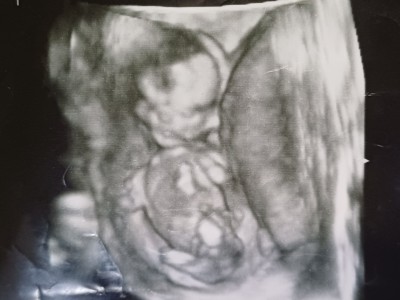

Kızlar sizce ne cinsiyeti doktor tahminim var ama söylemek için erken

image

dedi haftaya gideceğim ama merak ediyorum

12+3  haftaliktim canm gittiğimde